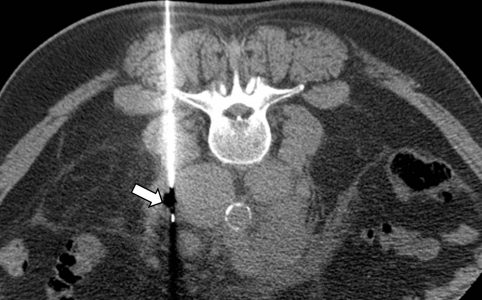

Η διαδερμική βιοψία είναι μια ελάχιστα επεμβατική μέθοδος λήψης υλικού από τον όγκο για κυτταρολογική και ιστολογική εξέταση από εστιακές αλλοιώσεις του ήπατος, του πνεύμονα, του μαστού, του νεφρού κλπ. Συνιστάται από τον κλινικό ιατρό ανάλογα με το είδος και το μέγεθος της βλάβης και πραγματοποιείται με ασφάλεια από επεμβατικό ακτινολόγο συνήθως με την καθοδήγηση αξονικού τομογράφου ή υπερήχων. Στη σύγχρονη ογκολογική θεραπεία, όπου γίνεται προσπάθεια καταπολέμησης του καρκίνου σε μοριακό επίπεδο, κρίνεται αναγκαία η ακριβής ιστολογική ταυτοποίηση του όγκου, ώστε να εφαρμοσθεί εξατομικευμένη θεραπεία για το βέλτιστο αποτέλεσμα.

Σε έναν δεύτερο πυλώνα ογκολογικής θεραπείας η Επεμβατική Ακτινολογία μπορεί να εφαρμόσει τοπικοπεριοχική θεραπεία καταστροφής των καρκινικών κυττάρων με τεχνικές είτε διαδερμικής κατάλυσης (Ablation) είτε διαδερμικού ενδαγγειακού χημειοεμβολισμού (TACE). Στην περίπτωση της κατάλυσης μπορεί να εφαρμοστεί σε καρκινώματα του ήπατος, του νεφρού, των οστών και των όγκων μαλακών μορίων και υπό προυποθέσεις στον πνεύμονα. Παθοφυσιολογικά βασίζεται στην τοπική καταστροφή των καρκινικών κυττάρων με τη δημιουργία ιδιαίτερα υψηλών θερμοκρασιών νέκρωσης εντός του όγκου. Αυτό επιτυγχάνεται με τοποθέτηση ειδικών βελονών-ηλεκτροδίων εντός του όγκου υπό ακτινολογική καθοδήγηση. Τα ηλεκτρόδια αυτά παράγουν υψηλή θερμοκρασία είτε με τη βοήθεια ραδιοσυχνοτήτων (RF ablation) είτε με τη βοήθεια μικροκυμάτων (MW ablation) και προκαλούν πηκτική νέκρωση των καρκινικών κυττάρων χωρίς να επηρεάζουν τα φυσιολογικά κύτταρα.